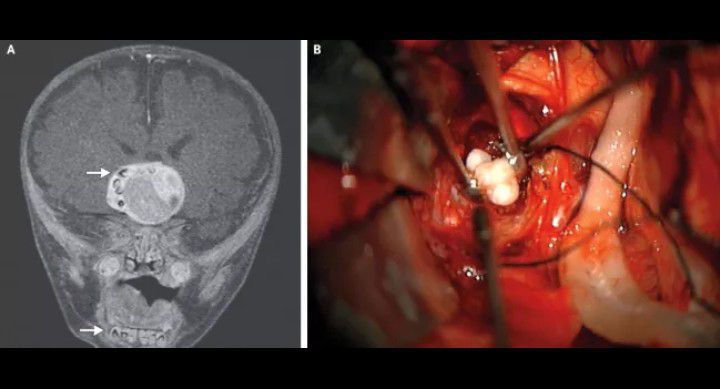

It's not entirely unusual for a 4-month-old baby to have a few teeth, unless those teeth are lodged in the baby's brain. An infant in Maryland had teeth form in his brain as a result of a specific type of rare brain tumor. Doctors were able to remove the tumor and the boy made a full recovery, according to a report published in the New England Journal of Medicine in February 2014. Doctors suspected something might be going on inside the boy's brain when his head appeared to grow faster than was usual for his age. A scan of the child's brain revealed a tumor that contained what looked like teeth normally found in the lower jaw. And indeed, when doctors removed the tumor they extracted several fully formed teeth with it. While teeth do sometimes appear in tumors, the type of tumor removed from the infant's brain — a craniopharyngioma — wasn't known to host these strange additions. By: https://www.livescience.com/37919-oddest-medical-case-reports.html